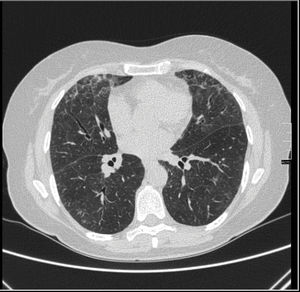

We present the case of a 63-year-old woman with a history of repetitive UTI, with no other relevant medical history. Prophylaxis with nitrofurantoin had been initiated a year prior to the presentation of symptoms. She was referred to the rheumatology department for migratory asymmetrical arthralgias of 4-month onset. During examination she referred to dyspnoea with moderate effort which had appeared after the arthralgias. Auscultation revealed bilateral crackling sounds. A chest X-ray showed a bilateral interstitial pattern and high resolution computerised tomography (HRCT) showed ground glass areas corresponding to acute/sub acute interstitial pneumonia (Fig. 1). Blood tests highlighted GOT 360U/l, GPT 432U/l and GGT 279U/l with normal abdominal ultrasound. The hepatropos virus serology and autoimmune antibody study tested negative. Autoimmunity studies detected ANCA+ 1/640 perinuclear staining (negative anti-myeloperoxidase and anti-proteinase 3). Due to these findings toxicity by nitrofurantoin was suspected and the drug was withdrawn. Treatment with prednisone was established, with a good response at respiratory level, a drop in hepatic enzymes and a complete resolution of arthralgias. During follow-up, the transaminase values remained normal, respiratory symptoms disappeared and posterior lung imaging tests were normal. The arthralgias abated and the ANCAs tested negative.

There have been case reports of concomitant pulmonary and hepatic toxicity attributed to the use of nitrofurantoin.3 Pulmonary toxicity and hepatic toxicity have 2 types of presentations: acute and chronic. Chronic pulmonary toxicity symptoms develop after several months of treatment. The most common are dyspnoea, irritative cough and fatigue. Crackling sounds, especially around the lung bases4 are usually the result of auscultation. All types of radiographic anomalies in most patients exist, mostly in inferior and bilateral fields. In the HRCT scan ground glass areas may be observed, together with septal enlargement and traction bronquiectasias.5